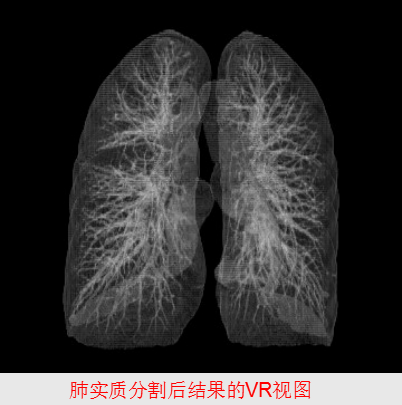

6、容积重现(VR)

VR是沿着虚拟操作者视线方向,将容积数据的所有体素的颜色和透明度的进行融合后,投射到屏幕上,实现三维显示。

优势:最大限度的保留了原始数据的细节,能够显示具有高质量的三维立体空间关系组织,而且操作简便。

用途:用于血管、骨骼、关节、尿路、支气管树、肌束的三维显示。

肺

肺癌的发病率和死亡率持续上升。

肺癌在男性肿瘤疾病中已居首位,在女性中仅次于乳腺癌。

我国肺癌患者居世界首位。

有效手段是“早期发现、早期诊断、早期治疗”。

X射线和CT。

肺CAD

-

肺功能分析

-----肺功能定量分析

-----肺气肿检测

-

肺结节检测

肺功能分析

肺功能定量分析

平均CT值、容积、标准方差、面积、气体容积、组织容积、组织重量、密度以及不同像素区间的百分比。

肺气肿检测

包括肺气肿区域检测和肺气肿定量分析,其定量分析指标有肺气肿体积、肺气肿区域百分比、严重程度和是否存在肺大泡。

肺气肿的CT影像表现为灰度值低于肺实质的黑色大泡。一般采取基于图像灰度的方法检测肺气肿。